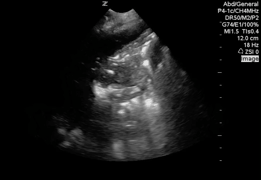

QA of the Day: pneumonia with air bronchograms, effusion #pocus #foamus #foamed